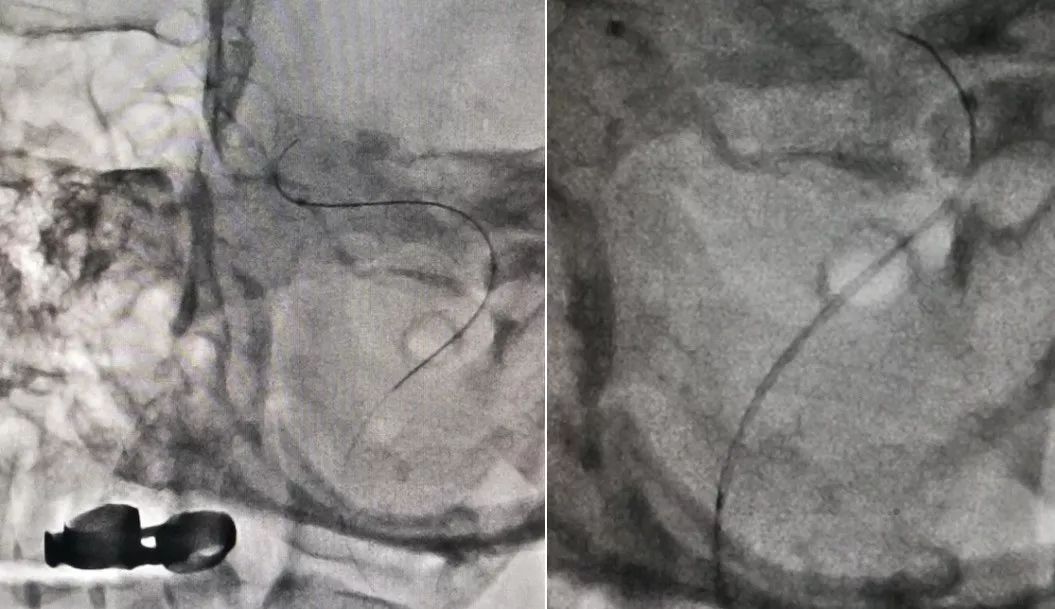

1、局麻后右侧股动脉穿刺置入6F动脉鞘,泥鳅导丝导引下6F导管超选至左侧颈内动脉起始段,造影示左侧颈内动脉C1段夹层动脉瘤。因我院机器未安装三维测试,运用圆规和尺子测量,得出血管直径10.5 mm,6F导引导管直径0.45 mm,6F导引导管实际管腔直径2.12 mm,根据公式计算2.12/0.45=X/10.5 X=4.946 mm ;考虑血管实际直径约5.0 mm,因此选择5.5 mm*35 mm Tubridge支架(图4)。

图4

2、路图下Traxcess-14微导丝携T-track微导管,小心越过瘤颈,置于颈内动脉C2段以远。以Tubridge中间标记点位于动脉瘤颈部为标记,将Tubridge(5.5 mm*35 mm)支架缓慢释放,完全覆盖瘤颈(图5)。

图5